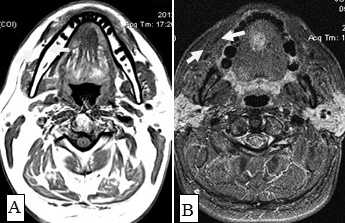

Рис.1. Пациент Ж., 58 лет. МСКТ ротоглотки в аксиальной проекции: А - нативное исследование, В - с внутривенным болюсным контрастированием. Небольшая инфильтративная опухоль ротоглотки (левой небной миндалины Т1 стадии). Границы опухоли не дифференцируются, накопление контраста слабое (показатели плотности в нативной фазе исследования 45 ед.Н, после внутривенного болюсного усиления - 56 ед.Н). Определяется смещение левой стенки ротоглотки, сглаженность контура (стрелки)